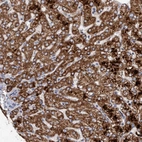

Immunohistochemistry analysis in human liver and placenta tissues using HPA023160 antibody. Corresponding DECR1 RNA-seq data are presented for the same tissues.